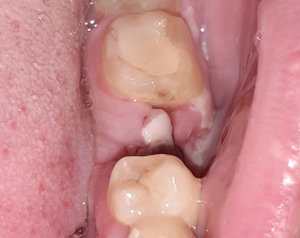

Удалила нижнюю восьмерку. Сгусток не образовался или образовался и быстро распался, потому что, когда я смогла открыть рот достаточно широко, чтобы что-то увидеть, лунка была глубокая и абсолютно пустая. Немного поднывала челюсть. Пошла к хирургу, который удалял, он посмотрел и сказал, что все нормально. Теперь вот прошло уже восемь дней. Лунка по-прежнему такая же глубокая и пустая, ноет, так и на стенках глубоко, в ней стенки все покрыты белым налетом! Я боюсь, что это альвеолит начинается, а сейчас майские праздники!

Подскажите, пожалуйста, может ли это быть нормальным процессом заживления (я хоть нервы поберегу, зная, точно болезнь это или нет - мне спокойнее точно знать) и если нет, то что делать? Особенно мешает, случайно попадающая в лунку еда. Она там засоряет и гниет (я не всегда сразу могу вытащить).

Остатки еды не нужно вытаскивать, выполняйте полоскания после приема пищи и все будет в порядке. Бело-серый налет это фиброзная ткань, норма. Не переживайте, еще покажитесь врачу через пару дней.